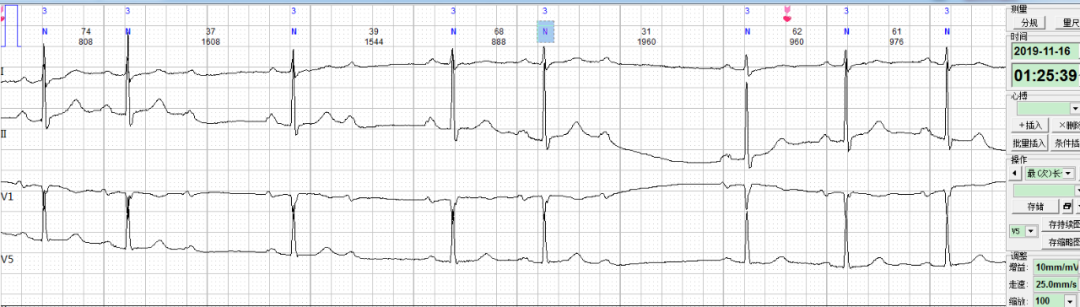

每日一图丨NO.676 房颤病人出现如下心电改变,请分析!乐普医疗AI关注2021-02-10 16:30 心电图解析(NO.675)今日读图(NO.676)患者史某,女,81岁,住院患者。心电监护到如下片段,如何分析诊断?诊断完毕后要记得将答案写在留言区哦 浏览 16点赞 评论 收藏 分享 手机扫一扫分享分享 举报 评论图片表情视频评价全部评论推荐 每日一图丨NO.679 71岁男性患者出现如下心电改变,请分析。乐普医疗AI0每日一图丨NO.646 患者出现如下心电改变,如何诊断?乐普医疗AI0每日一图丨NO.682 患者出现如下心电改变,如何诊断?乐普医疗AI0每日一图丨NO.628 患者出现严重异常心电改变,请分析!乐普医疗AI0每日一图丨NO.658 患者的心电图出现如下改变,请诊断?乐普医疗AI0每日一图丨NO.680 窦性心律患者出现如下心电改变,如何诊断?乐普医疗AI0每日一图丨NO.675 请判断患者出现何种心电异常改变?乐普医疗AI0每日一图丨NO.663 出现如下心电情况吗,什么原因所致?乐普医疗AI0每日一图丨NO.664 同一患者出现如下六幅心电图改变,如何判断?乐普医疗AI0每日一图丨NO.625 一位九岁儿童出现心电异常,请判断!乐普医疗AI0点赞 评论 收藏 分享 手机扫一扫分享分享 举报